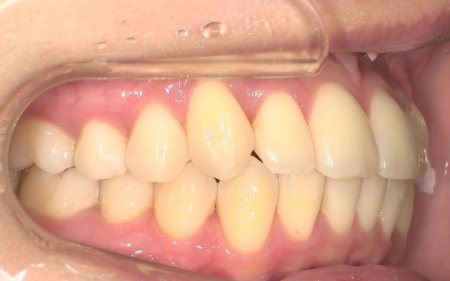

20代女性 八重歯と歯並びの乱れをマウスピース矯正装置で改善した症例

拝見したところ、歯が正しく並ぶためのスペースが不足しており、歯が重なって生えてしまう叢生(そうせい)の状態が全体的に見られました。

特に上下の糸切り歯が外側にずれている、いわゆる八重歯が目立っています。

患者様の場合は上下あごの位置関係から噛み合わせに大きな問題はなく、横顔のバランスや鼻先とあごを結んだEラインにも目立った乱れは見られませんでした。